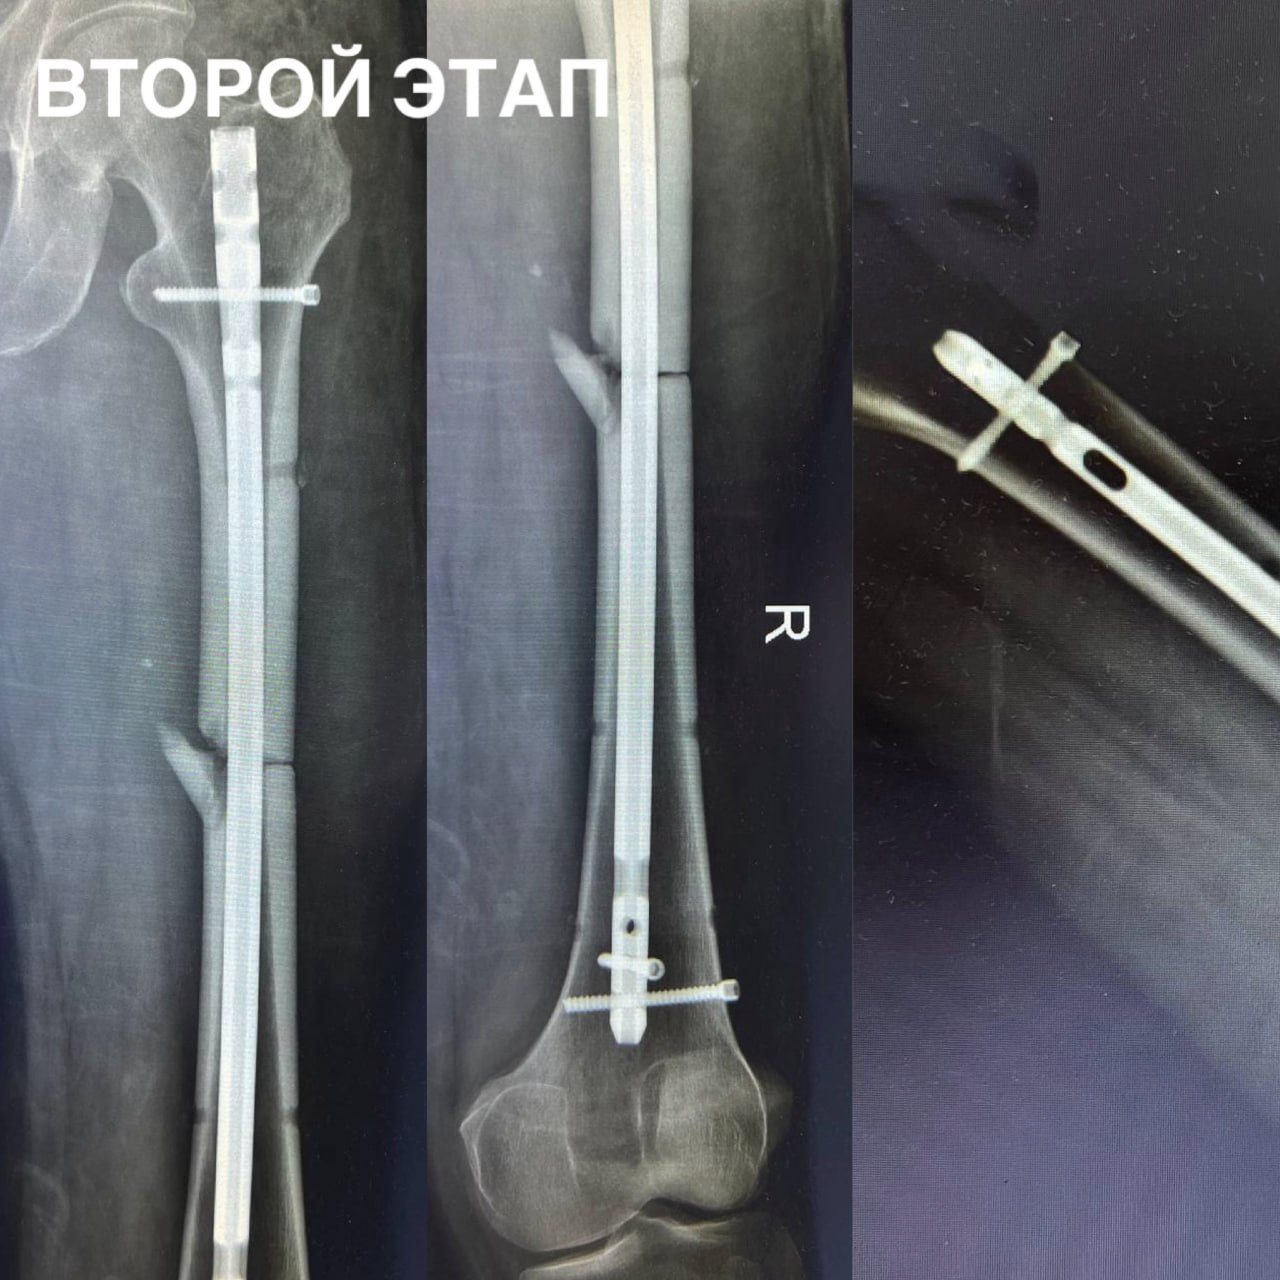

55-летний пациент поступил в городскую больницу скорой помощи с открытым оскольчатым переломом правой бедренной кости со смещением костных отломков. Врачи быстро стабилизировали состояние мужчины и буквально заново, как пазл, собрали и кость.

Сейчас ставрополец готовится к выписке. В краевом минздраве отметили профессионализм операционной бригады. В неё входили завотделением сочетанной травмы Артур Апагуни и врачи-травматологи-ортопеды Виктор Посух и Михаил Даньшин.